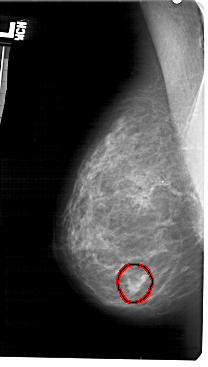

A_1362_1.LEFT_CC

LEFT_CC LINES 4756 PIXELS_PER_LINE 2761 BITS_PER_PIXEL 12 RESOLUTION 43.5 OVERLAY

FILE: A_1362_1.LEFT_CC.OVERLAY

TOTAL_ABNORMALITIES 1

ABNORMALITY 1

LESION_TYPE MASS SHAPE IRREGULAR MARGINS ILL_DEFINED

ASSESSMENT 4

SUBTLETY 5

PATHOLOGY BENIGN

TOTAL_OUTLINES 1

BOUNDARY